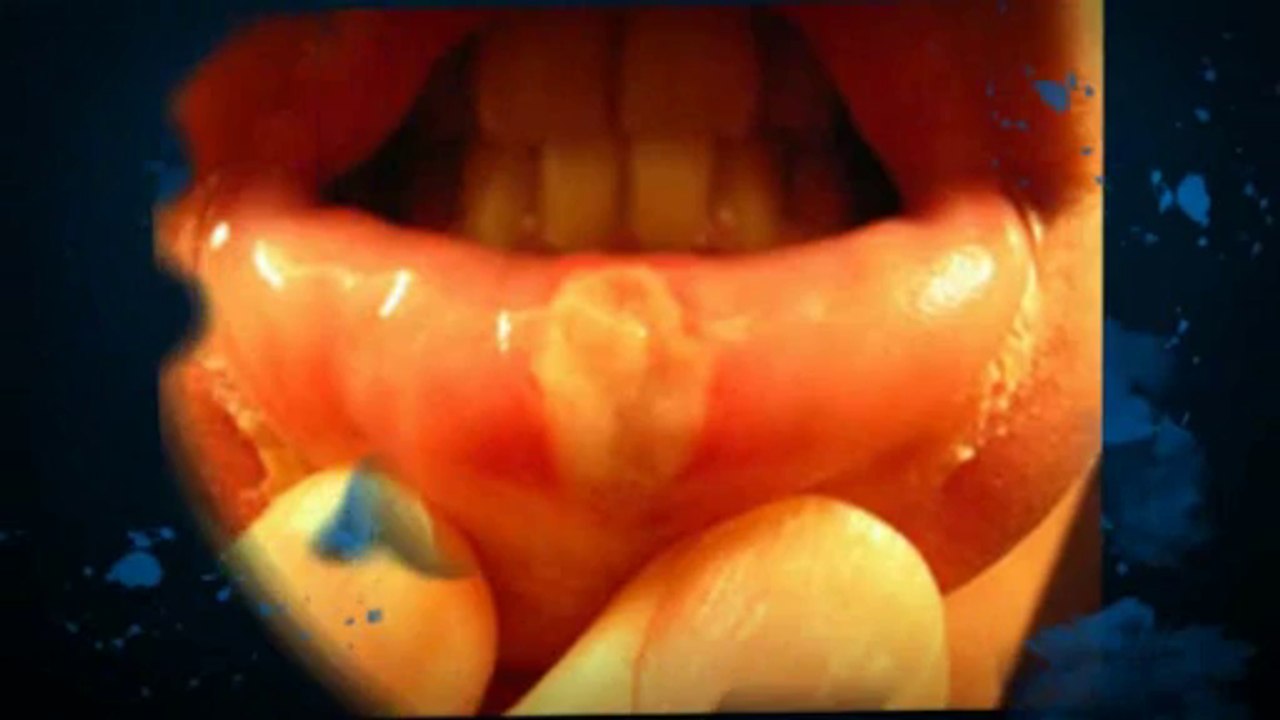

Canker Sores - Natural Ayurvedic Home Remedies 1:51

Canker Sores - Natural Ayurvedic Home Remedies